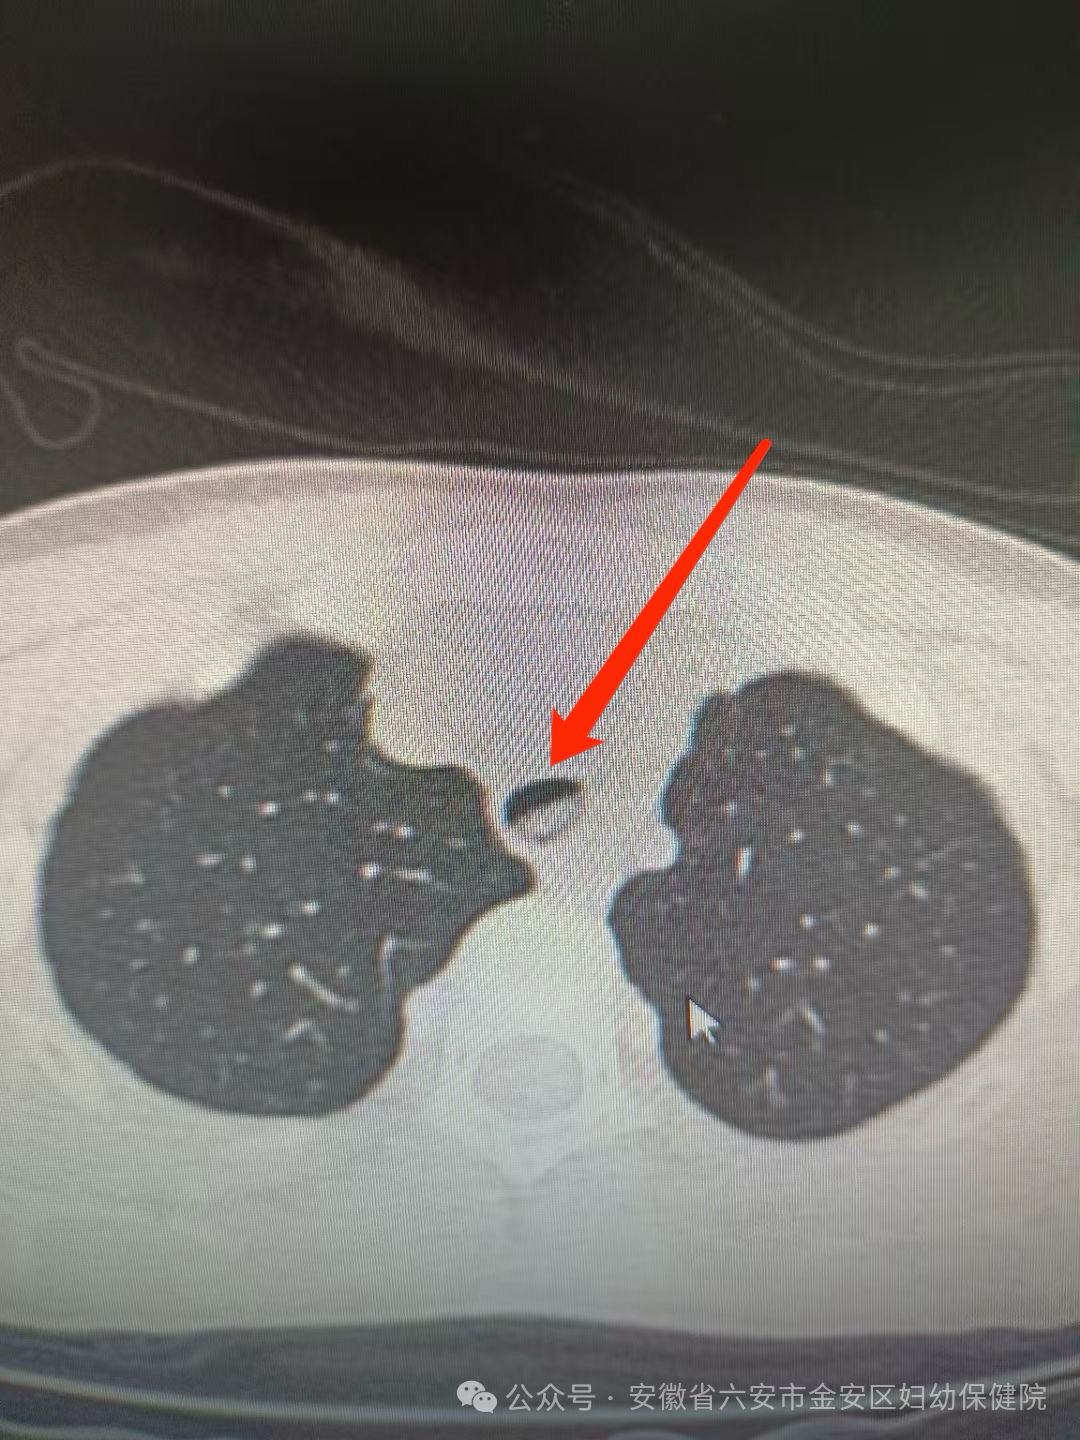

入院时,该患儿SPO2 77%,P 120次/分,R 30次/分。神清,精神差,慌张面容,余未见明显异常,胸部CT平扫+气道重建像显示:主气管内(主动脉弓上方层面)见类卵圆形高密度影,边界模糊;异物可能性大,考虑到患儿病情危急,周一杰主任团队迅速反应,立即为患儿实施经支气管镜气管内异物取出术。手术操作过程仅仅耗时3分钟取出异物,手术过程顺利,患儿生命体征平稳。